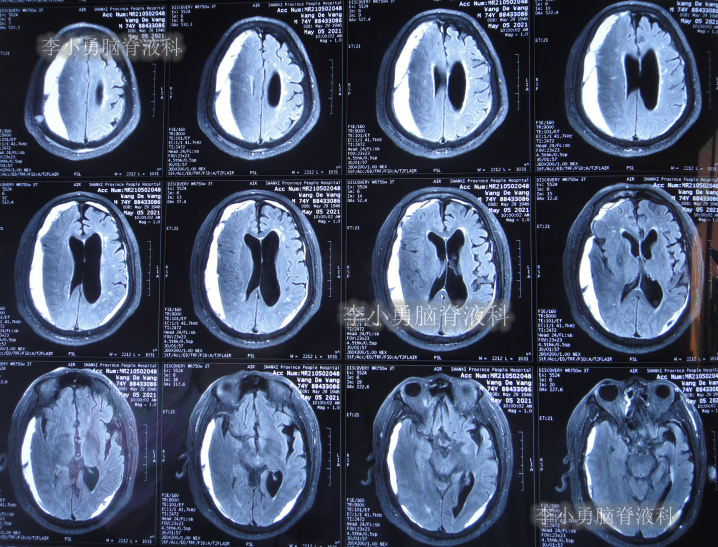

2021年5月5日(腰大池腹腔分流术后38天,即拔除硬膜下血肿引流管16天),查头部核磁和腰椎核磁(图-10、图-11)后认为可能是颅内感染或和堵管。

图-10:2021年5月5日头部核磁

图-11:2021年5月5日腰椎核磁